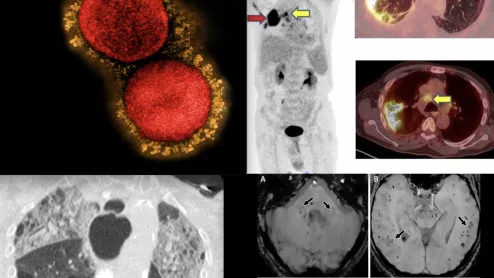

As cancer therapies become increasingly targeted and complex, the need for sophisticated cardiovascular monitoring has grown in parallel. Cardiovascular Business spoke with Daniel Addison, MD, director of the cardio-oncology program at The Ohio State University and chair of the American Heart Association’s (AHA) Cardiac Imaging Committee, who said the use of multimodality imaging is transforming how clinicians manage cardiovascular risk in cancer patients and survivors.

“Multimodality imaging in cardio-oncology is something many of us in the field are truly excited about," Daniel Addison, MD, told Cardiovascular Business. He noted that modalities other than echocardiography are starting to play a much larger role in the treatment of these patients.